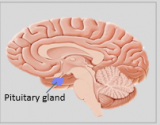

La neuroanatomie est la branche de l'anatomie qui étudie l'anatomie du système nerveux, c'est-à-dire la structure, la fonction et l'organisation du système nerveux.

Le système nerveux est l'un des systèmes les plus complexes du corps humain, et il comprend le cerveau, la moelle épinière, les nerfs périphériques et les ganglions nerveux. La neuroanatomie s'intéresse à la manière dont ces structures sont reliées les unes aux autres, comment les signaux sont transmis entre les cellules nerveuses, et comment les différentes parties du système nerveux travaillent ensemble pour contrôler les fonctions corporelles et cognitives. Les neuroanatomistes utilisent des techniques d'imagerie avancées, comme l'imagerie par résonance magnétique (IRM), la tomographie par émission de positons (TEP) et la microscopie pour visualiser les structures et les fonctions du système nerveux.